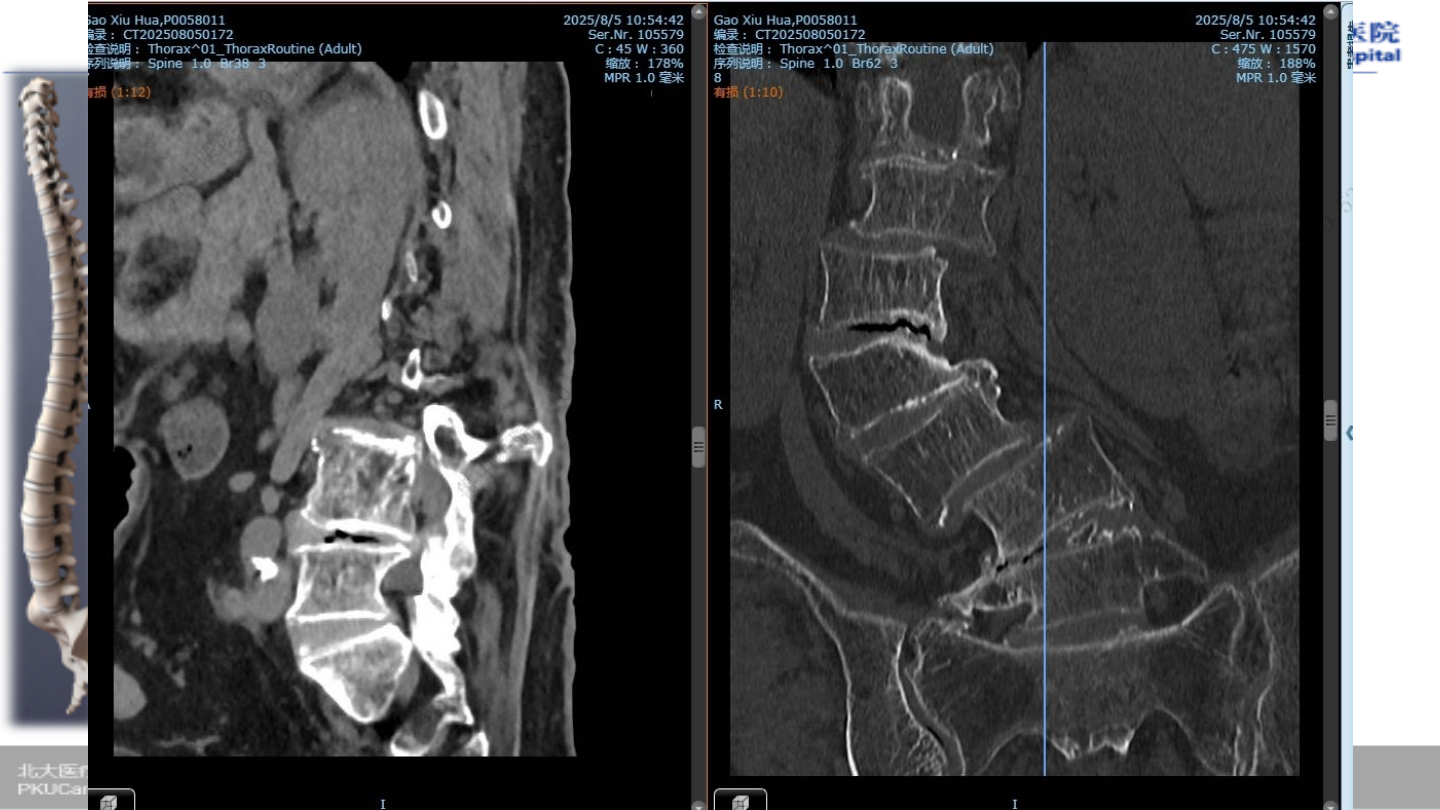

术前腰椎

CT